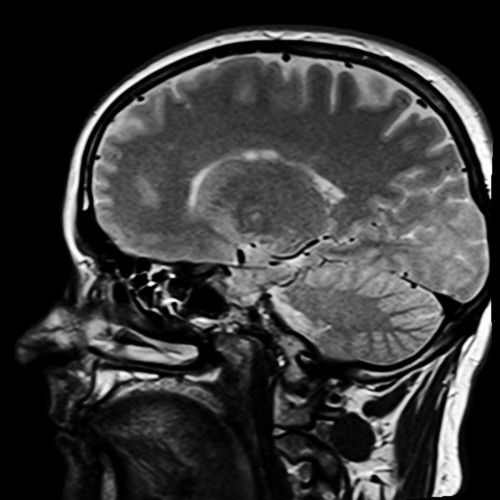

Manipulating alpha waves with LED illumination and audio stimulation can change the perception of pain. Credit: University of Manchester release.